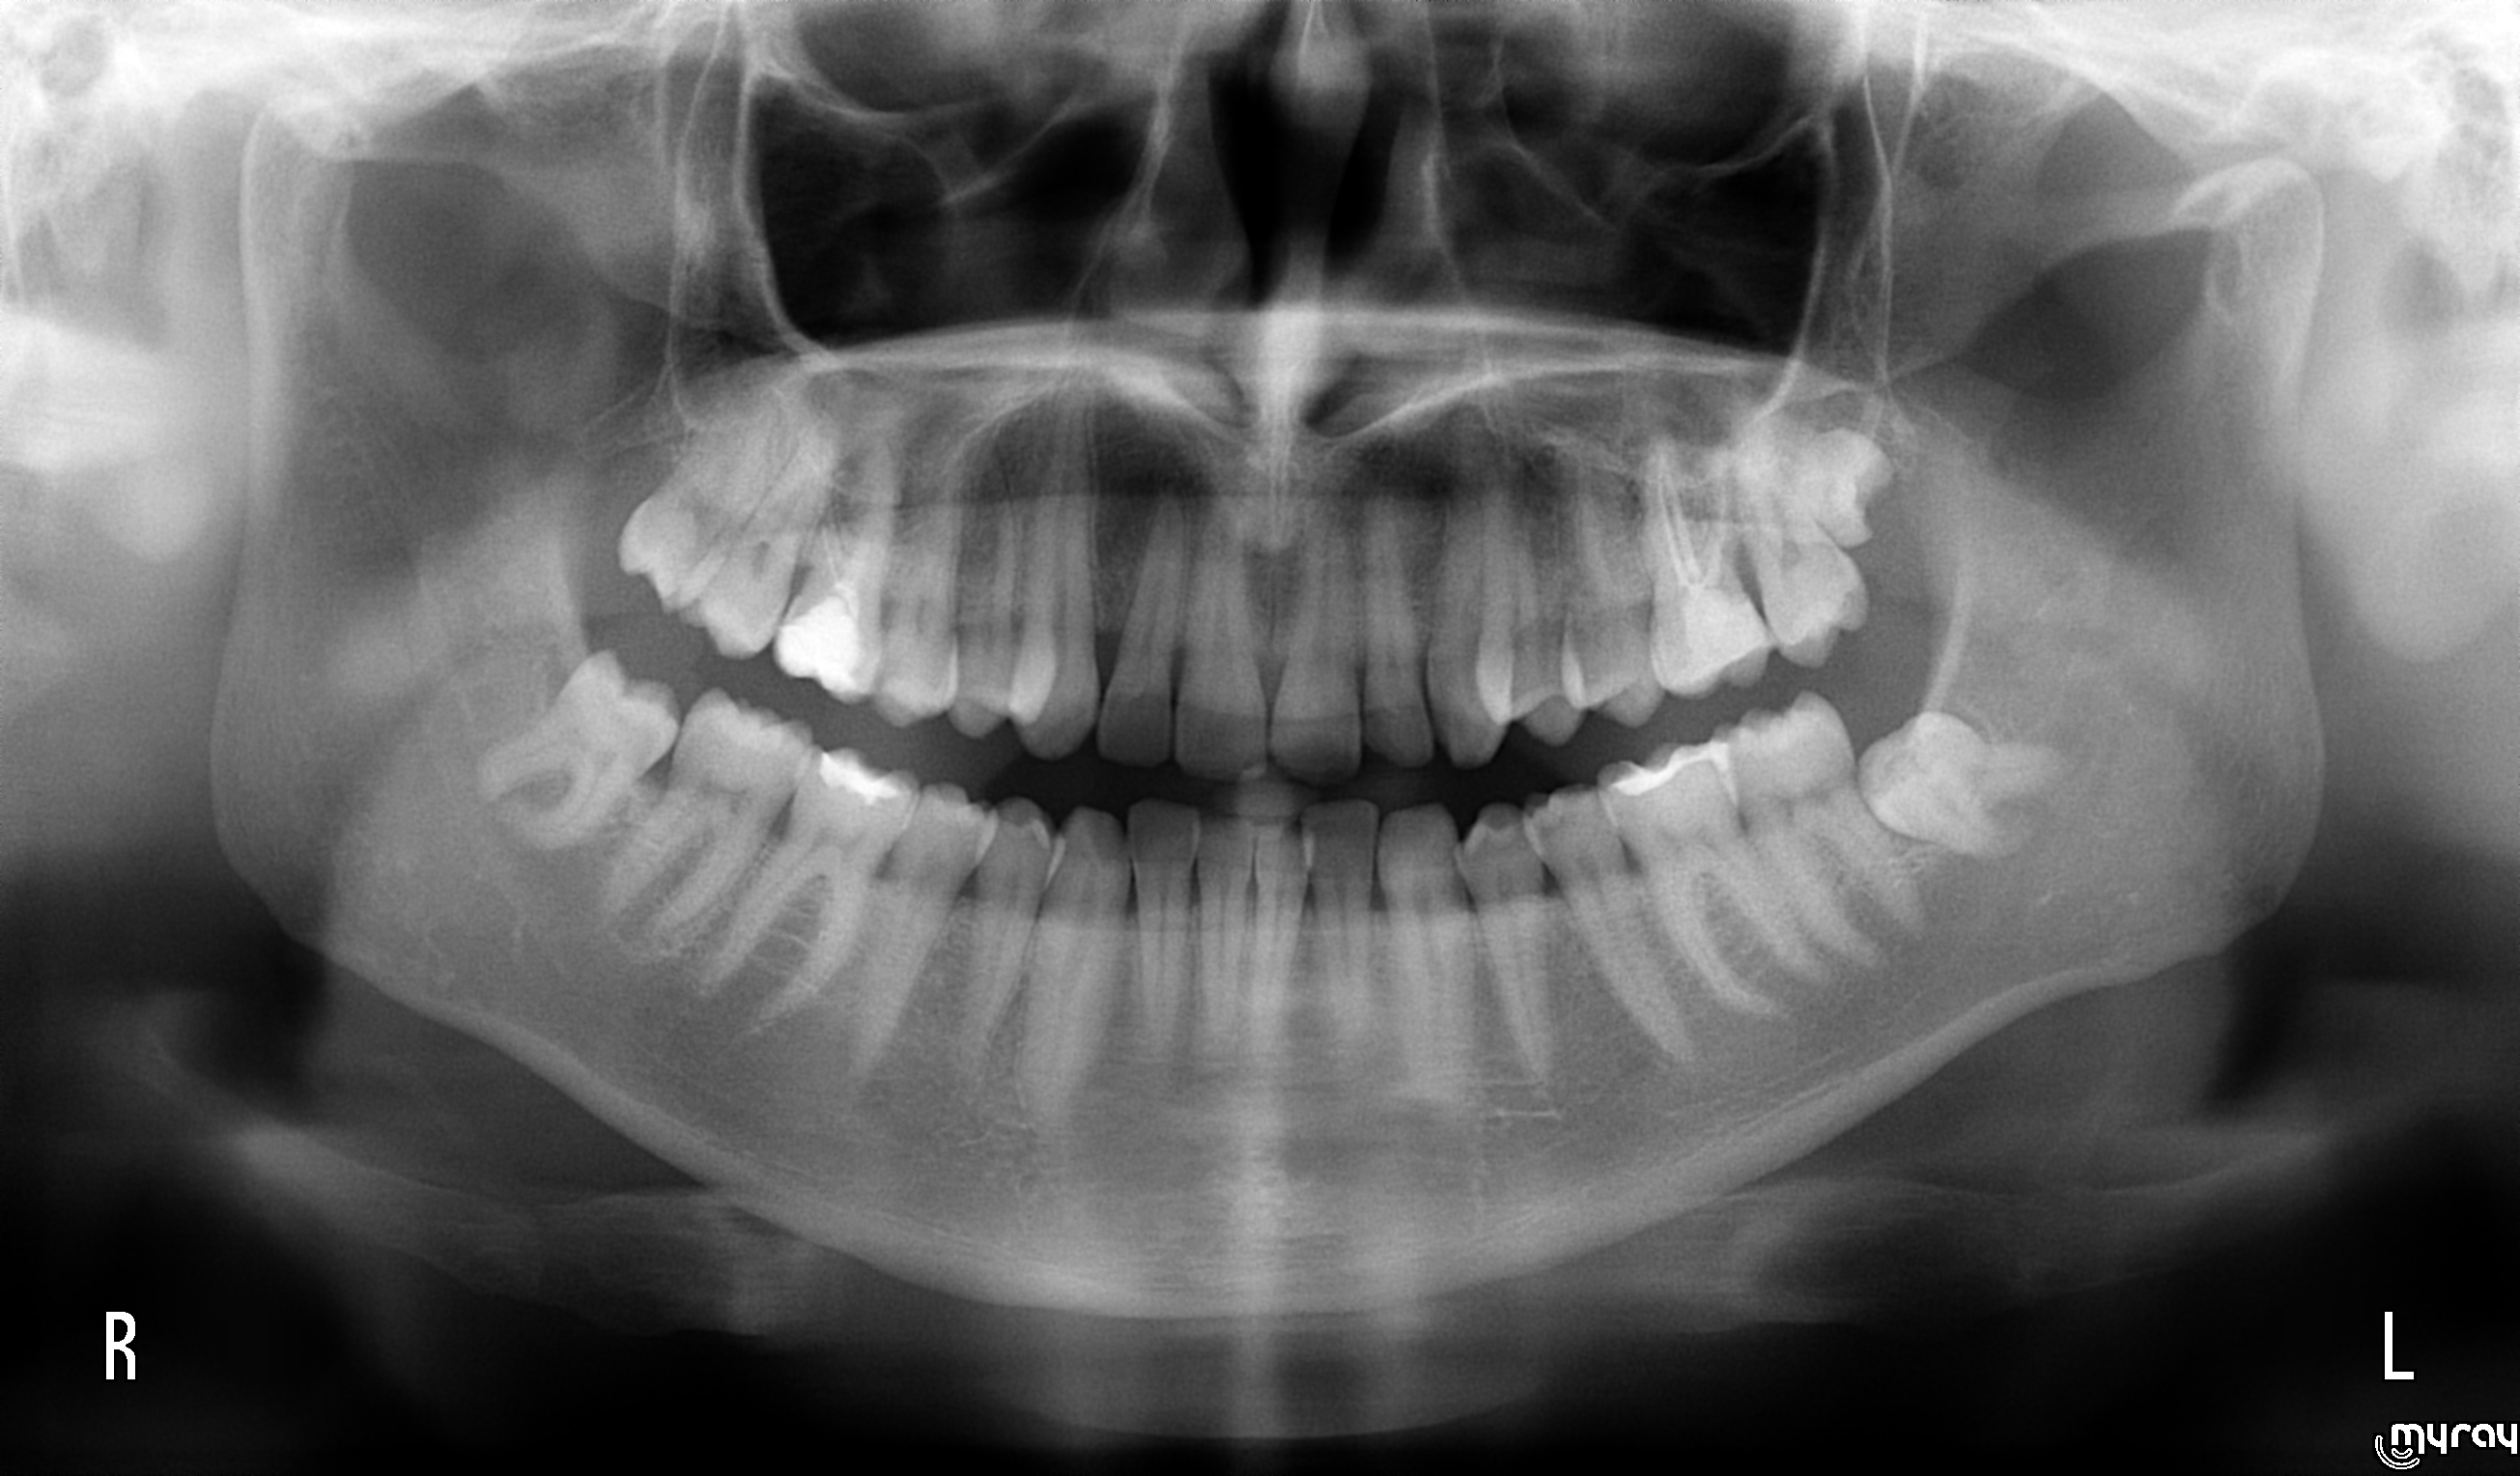

La chirurgia piezoelettrica permette di effettuare una serie di interventi in maniera poco traumatica, precisa e sicura sulle ossa mascellari, nell'assoluto rispetto delle strutture vascolari e nervose situate in prossimità nella zona d'intervento. Il caso, giunto alla nostra osservazione, riguardava un giovane paziente di sesso maschile che presentava una intensa sintomatologia algica da pericoronarite del 4.8. All'esame OPT il 4.8 presenta la radice mesiale fortemente ricurva ad angolo retto ed una contiguità delle radici con il canale mandibolare. Si è proceduto in una prima fase allo scollamento di un lembo mucoperiosteo e con l'ausilio del piezosurgery ad una osteotomia che ha facilitato l'avulsione del 4.8 nel rispetto delle strutture nobili e delicate contigue.